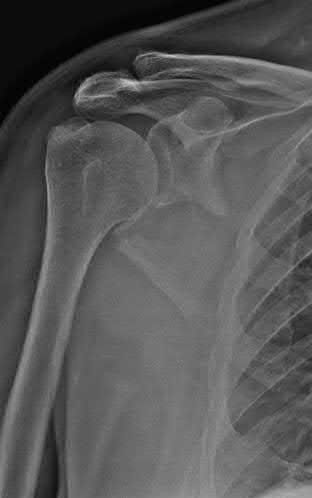

Question 12

A 55-year-old patient presents with a slowly enlarging, painful mass in the proximal humerus.

Biopsy reveals a hyaline cartilage matrix with cellular atypia, confirming a diagnosis of central conventional chondrosarcoma. Which of the following genetic mutations is most frequently identified in this specific tumor?

Explanation

Mutations in the isocitrate dehydrogenase genes, IDH1 and IDH2, are found in up to 50-60% of central conventional chondrosarcomas and enchondromas. EXT1 and EXT2 mutations are characteristic of multiple hereditary exostoses (osteochondromas). GNAS mutations are seen in fibrous dysplasia. TP53 and RB1 mutations are hallmark aberrations in osteosarcoma.